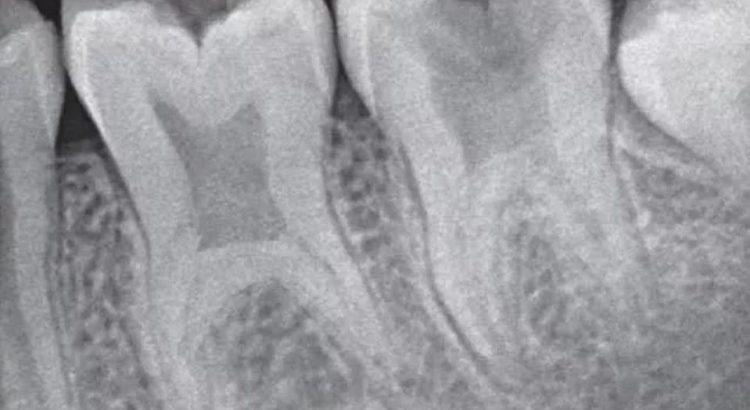

Pada gigi yang mengalami taurodontia, bentuknya terlihat lebih persegi atau silinder daripada gigi normal. Ruang pulpa membesar secara vertikal hingga ke area akar gigi, menyebabkan bagian akar menjadi lebih pendek dan bagian mahkota gigi terlihat lebih panjang dari biasanya.

Kelainan ini umumnya terdeteksi melalui pemeriksaan radiografi (rontgen gigi), karena bentuk luar gigi tampak normal dari permukaan.